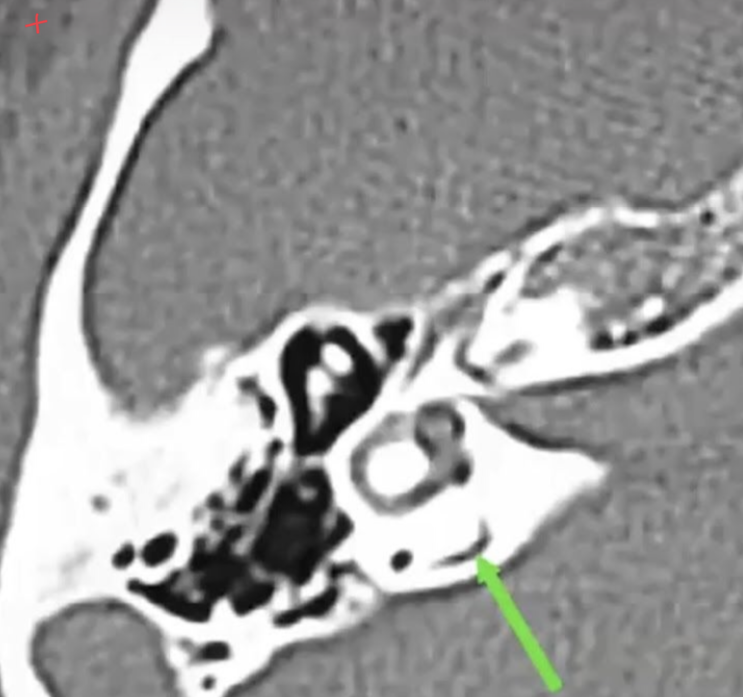

Above which width you consider a pathological vestibular aqueduct?

Whats the main associated symptom?

?